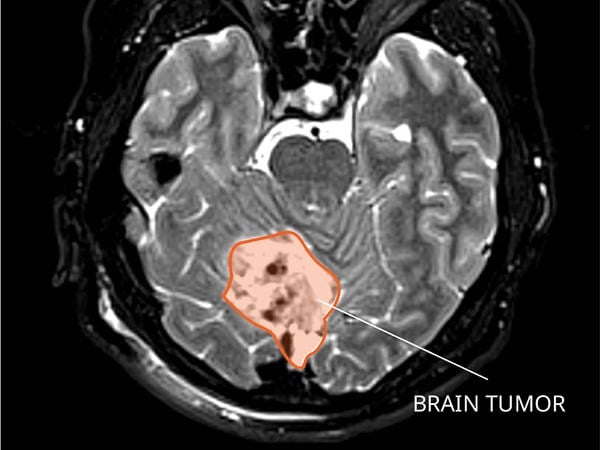

High-grade gliomas are aggressive brain tumors that can strike at any age, but in infants, they have historically carried a grim prognosis—often limiting life expectancy to just two years or less. These tumors grow rapidly in the developing brain, causing symptoms like irritability, vomiting, enlarged head size, and developmental delays.

Dr. Clarke’s research, part of an international collaboration, pinpointed a molecular subgroup of these tumors occurring exclusively in infants under 12 months. This subgroup features distinct genetic markers that make the cancer cells vulnerable to already-approved targeted therapies—drugs originally developed for other cancers.

The study, contributing to a new chapter in the World Health Organization’s classification of brain tumors, involved detailed genomic analysis of infant gliomas. Researchers found that this subgroup lacks the aggressive features seen in older children and adults, responding instead to precision medicines that block specific cancer-driving pathways.